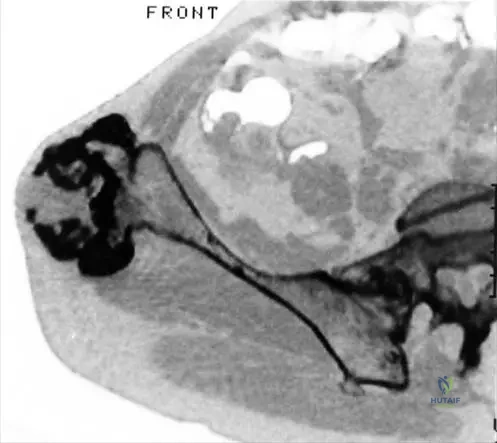

A 7-year-old girl with hereditary multiple exostoses is noted to have progressive bowing of her forearms and ulnar deviation of her wrists. Radiographs confirm multiple osteochondromas in the distal radius and ulna. Which of the following is a common associated deformity seen in HME affecting the upper extremities?

Correct Answer: B

Rationale: Severe deformation of forearms with bilateral elbow dislocation is a recognized complication of hereditary multiple exostoses, as shown in Fig. 1.53d. The bowing of the radius with ulnar deviation of the wrist and subluxation of the radiocarpal joint are also common. While other conditions listed can occur in the upper extremity, radial head dislocation (often leading to elbow dislocation) is a direct and common consequence of the growth disturbances caused by osteochondromas in the forearm in HME.

A 19-year-old female with hereditary multiple exostoses presents with a painful mass in her left groin region. A CT scan reveals an osteochondroma arising from the iliac bone. What is a potential complication of osteochondromas in the pelvic region?

Correct Answer: A

Rationale: Osteochondromas in the pelvic region, particularly those arising from the iliac bone (as shown in Fig. 1.55), can grow large and impinge on adjacent neurovascular structures. Sciatic nerve compression is a known complication, leading to pain, numbness, or weakness in the lower extremity. While bladder dysfunction could theoretically occur with very large pelvic masses, nerve compression is a more direct and common complication. The other options are less directly related to an iliac osteochondroma.